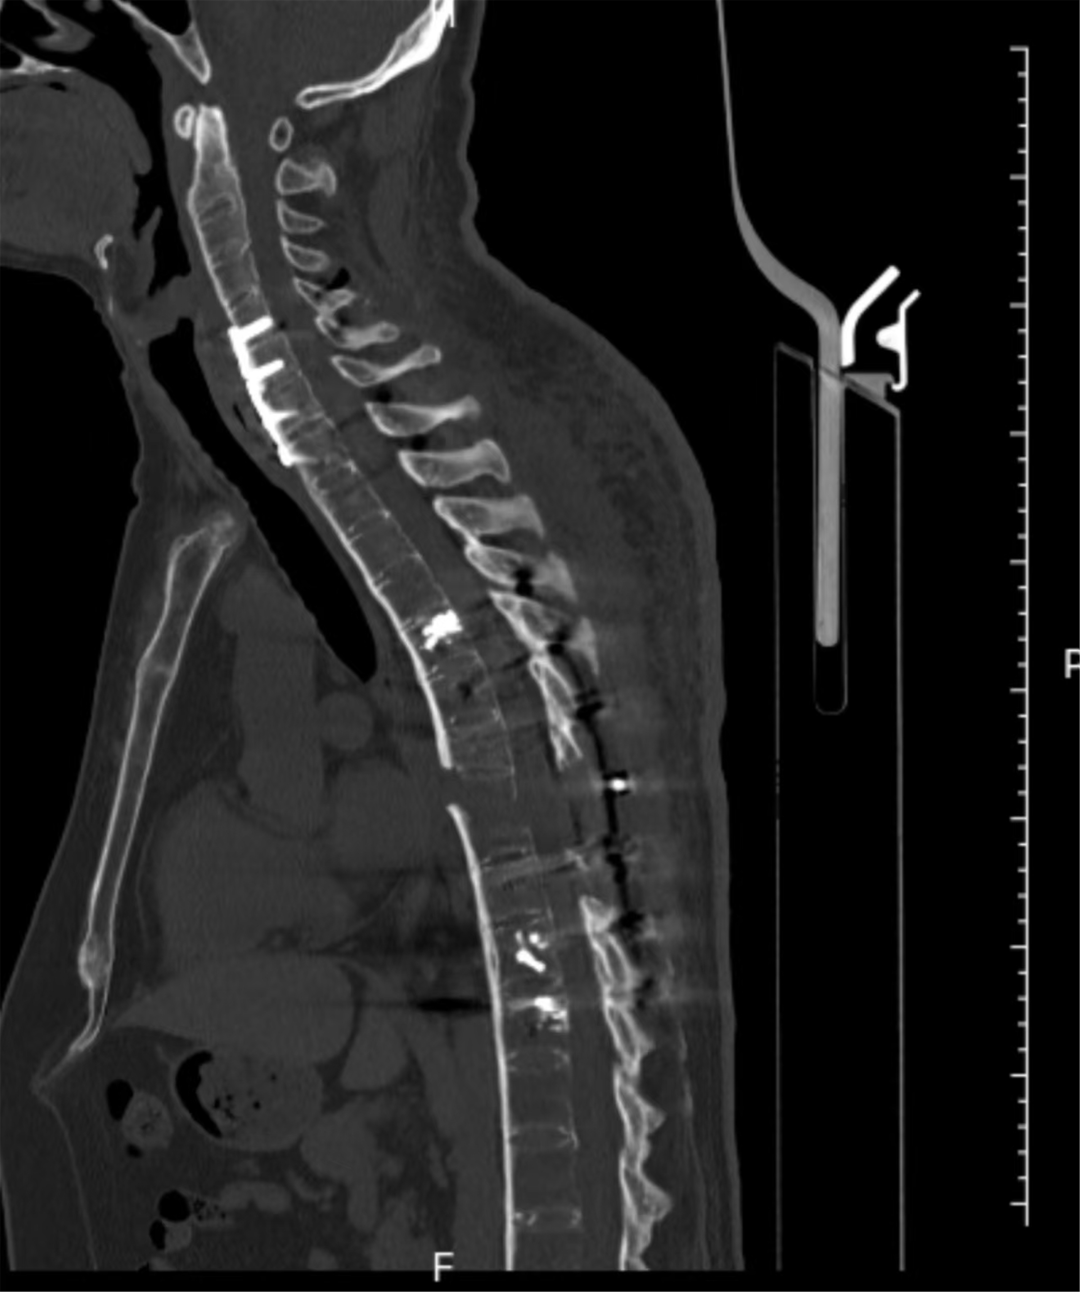

手术当日,多学科团队严阵以待,分阶段有序推进。先行仰卧位颈椎闭合复位,再通过颈前5厘米微创切口完成颈椎前路内固定,显著改善颈椎前方极度不稳定状况,重建颈椎前柱稳定性。随后,在神经电生理全程监测下,多学科协同完成Jackson床180°平稳翻转,成功破解术中核心高危难点。最后,经后正中入路开展颈椎后路固定,并对胸椎骨折完全脱位部位进行减压、精准复位与牢固内固定,彻底重建颈椎及胸椎脊柱正常序列。

经过13个小时的手术,患者的颈椎及胸椎脊柱序列得以重建

术后,患者经个性化康复治疗,脊柱序列恢复正常,无瘫痪及神经功能障碍加重。目前,患者正有序开展康复训练,即将重返正常生活。